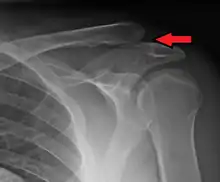

Type 3 AC joint separation on plain X ray

In a Type III AC separation both acromioclavicular and coracoclavicular ligaments are torn without significant disruption of the deltoid or trapezial fascia.[10] A significant bump, resulting in some shoulder deformity, is formed by the lateral end of the clavicle. This bump, caused by the clavicle's dislocation,[5] is permanent. The clavicle can be moved in and out of place on the shoulder. A radiographic examination will show the results as abnormal.